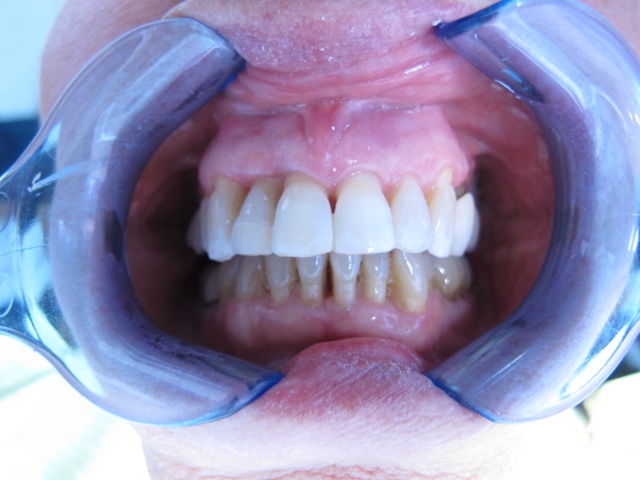

Arcade maxillaire avant traitement orthodontique, séquelles de maladie parodontale

Après traitement orthodontique et réalisation d’une attelle coulée collée (courtoisie Dr Patrick Fournier)